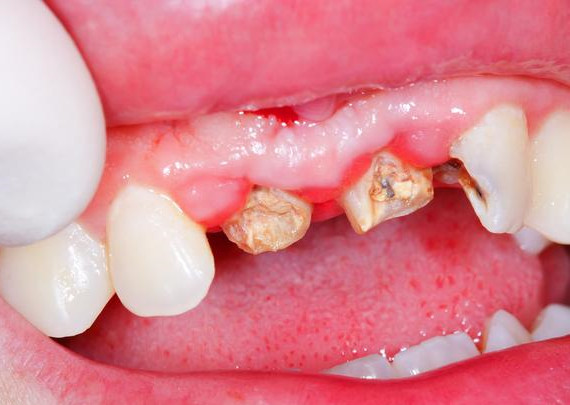

残根

牙齿连根龋坏,毫无保留价值。

治疗方式:烤瓷牙、种植牙